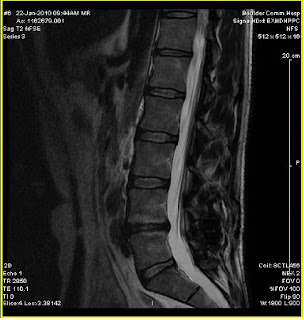

Had my 2 year follow up with MRI and X-ray's last week and I have posted the images below. The surgeon (Dr V) was surprised that the L4 and L5 bones showed signs of improved health ( 2 years ago they both took a beating from the wear and tear on them). The disc is still degenerating but it's seems to have slowed somewhat.

Below are the MRI and X-Ray images:

(MRI courtesy of BCH)